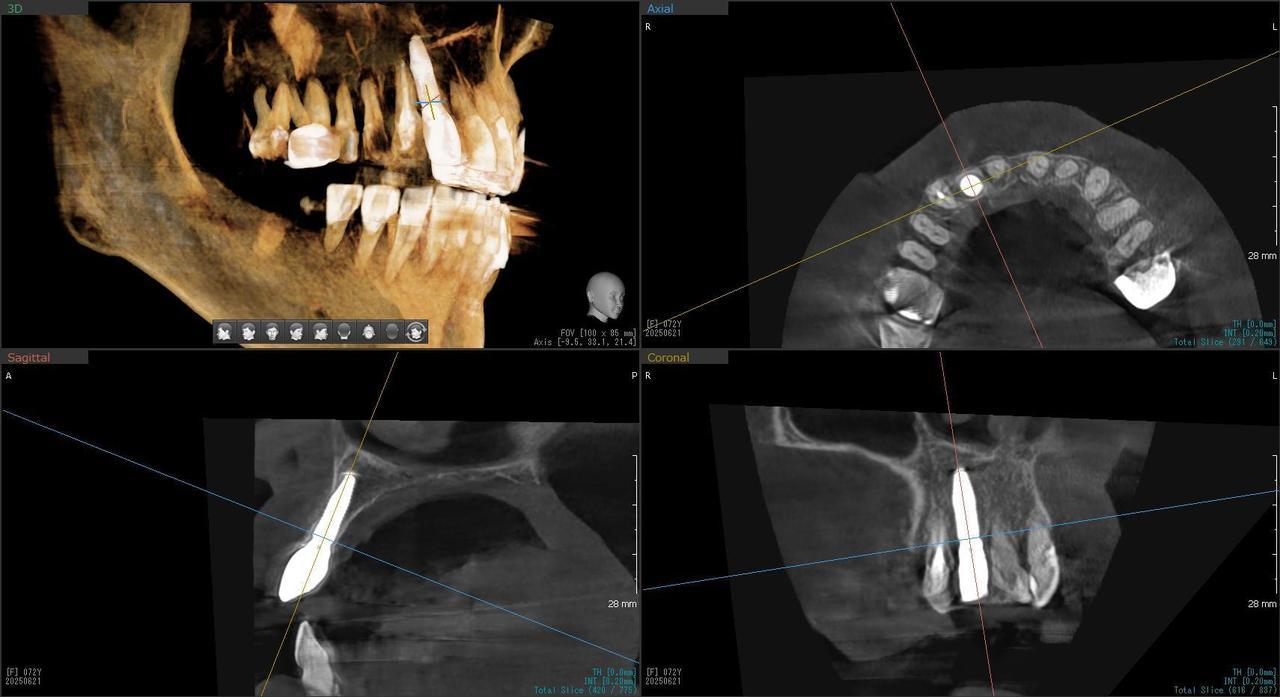

5.右上6番の歯根が破折したに大きな骨欠損を生じたケースに対して、通常なら、大幅な増骨手術(GBRとサイナスリフト)が必要で、最低1年は、かかるケースを、骨補填材なしで、インプラント埋入後、2.5か月で治療を終えたケース

症状としては、左上6番の歯根が歯根が破折したために、炎症が起き、上顎洞底までの及ぶ大きな骨欠損がおきていた、

治療法としては、動揺がひどくなってきて、炎症の症状もあったため、抜歯を希望。抜歯後にインプラント治療を希望したために、CTを撮影したところ、かなりの骨欠損が生じていた。インプラントは不可能か大幅な増骨手術が必要なるようなケースであったが、ご自分の骨が少し残っていた部分にエクストラワイドインプラントで固定をとることと、グラフトレスサイナスリフトを併用する計画を立て、インプラント埋入術を施行。2か月後、インプラントがデータ測定上安定したために、光学印象で印象を行い、2か月半後に上部としてジルコニアクラウンを装着して治療を終えています。

治療結果として、大幅な骨欠損があったが、2か月半という短時間で治療を終えることができた。通常のサイナスリフト等の大幅な増骨手術を行った場合、患者様に、肉体的、金銭的、時間的な負担をかけることになったが、グラフトレスサイナスリフトとエクストラワイドインプラントを使用することにより、そのことを避けることができた。

治療の期間・回数:治療回数インプラント埋入後6回

治療の価格:363000円(税込)

治療費の内訳:インプラント基本料(フィックスチャー(メガジェンインプラントANYONE) 及び手術費用、投薬費用、レントゲン費用、インプラント上部費用(アバットメントおよびジルコニアクラウンの費用用)330000円(税込み)左上6グラフトレスサイナスリフト費用 33000円(税込)

治療のリスクや副作用:手術後に、痛みや腫れ、出血、合併症などを引き起こす可能性があります。噛む感覚がご自身の歯と異なる場合があります。見た目がご自身の歯と異なる場合があります。手術後にメインテナンスを継続しないと、インプラントが抜け落ちる可能性があります。